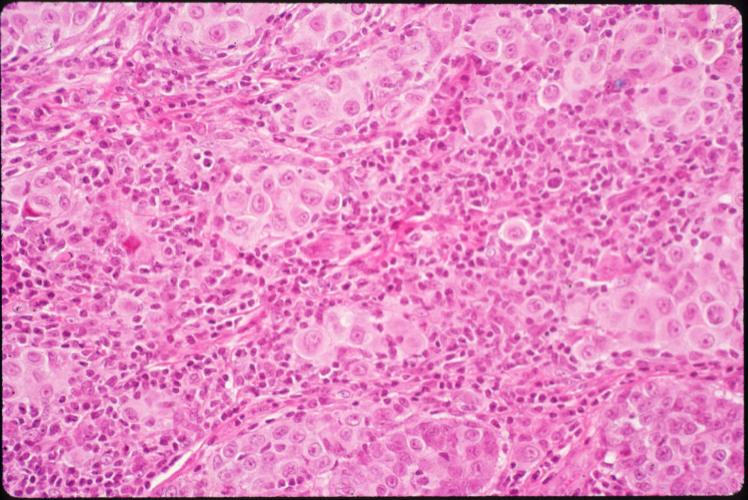

malignant-melanoma